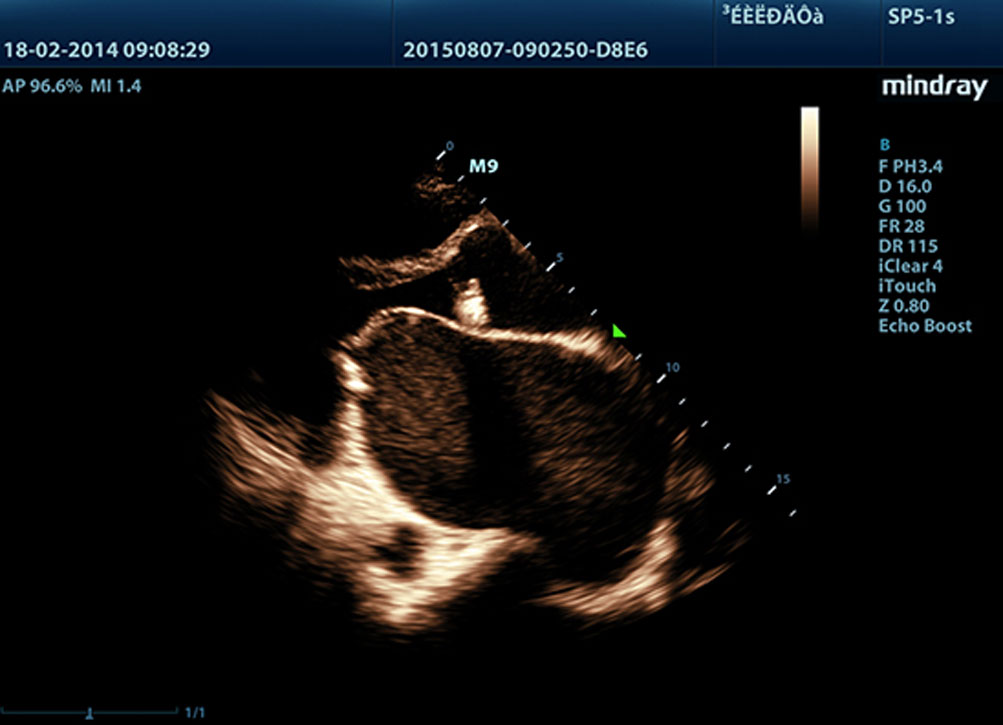

Echo Boost?

La tecnologĂa Ășnica de procesamiento de se?ales adaptativa de Mindray con detecciĂłn inteligente por eco ha sido dise?ada para utilizar la informaciĂłn nativa se?al-ruido con el fin de mejorar las se?ales de eco dĂ©biles suprimiendo al mismo tiempo el ruido y el desorden circundantes, proporcionando asĂ un brillo de imagen mĂĄs equilibrado y una visualizaciĂłn mejorada de las capas del miocardio.

LVO con ecocardiografĂa de estrĂ©s

Las capacidades superiores del M9 permiten la opacificaciĂłn LV durante el estrĂ©s, lo que mejora la discriminaciĂłn entre tejidos miocardiacos y coĂĄgulos de sangre y proporciona una mejor visualizaciĂłn de la superficie endocardiaca. La funciĂłn de ecocardiografĂa de estrĂ©s del M9 incluye un paquete completo para ecocardiograma de estrĂ©s farmacolĂłgico y de ejercicio. El paquete estĂĄ soportado por un sistema de informe flexible que puede ser optimizado para sus necesidades individuales.